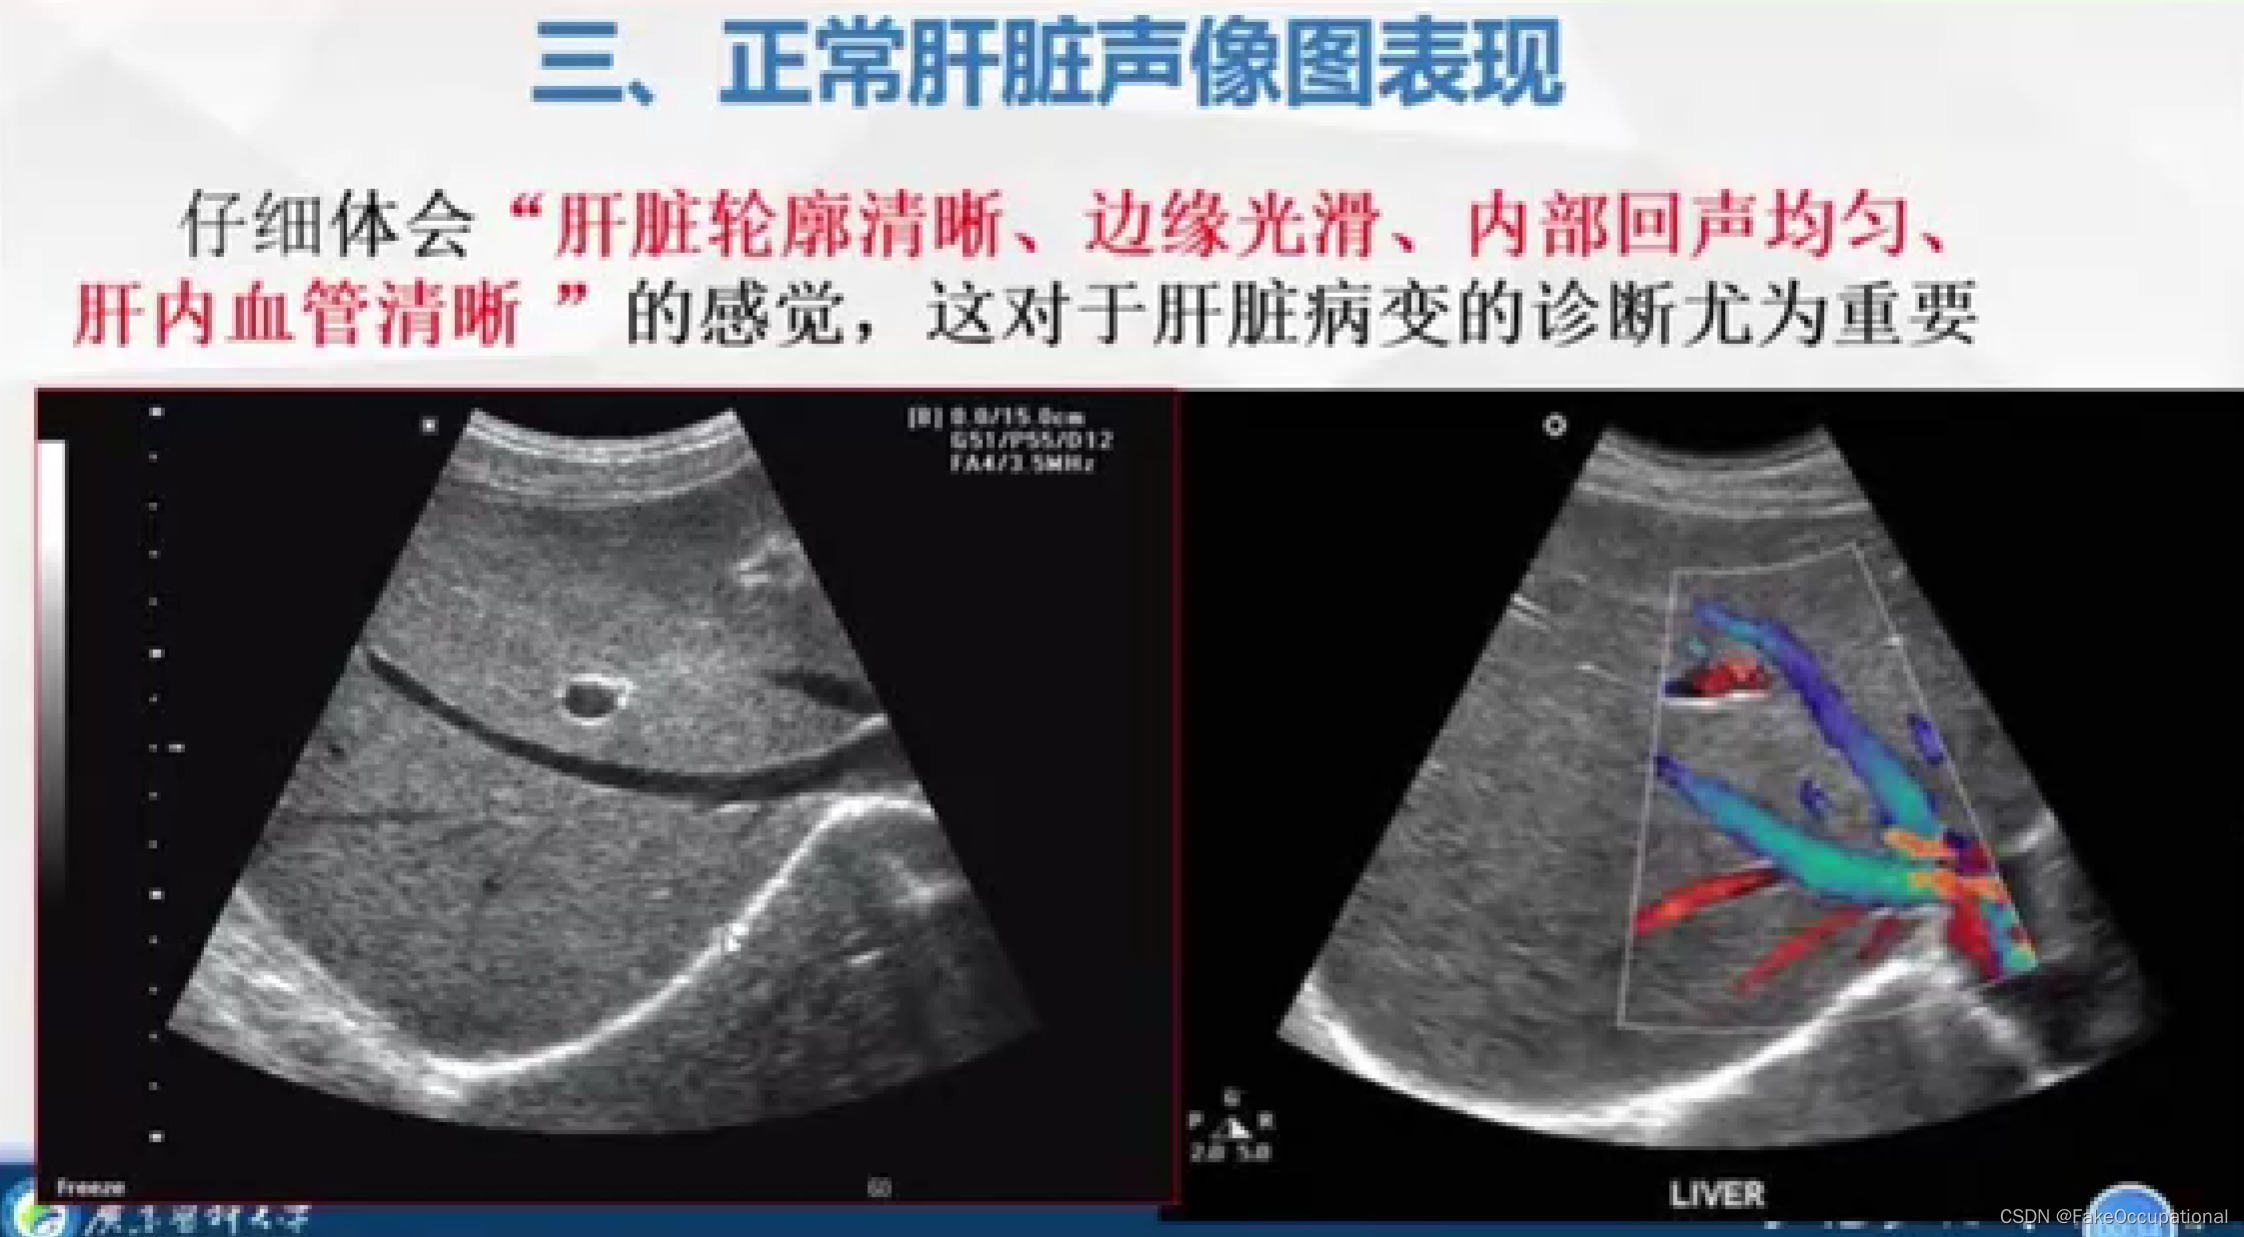

正常肝脏超声表现

- 超声更多起一个筛查的作用,定性需要造影或者其他设备的辅助